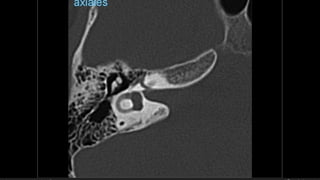

Evaluación Imagenologica

• #38 Izqu. AXIAL-- fxLongitudinal perdonan la capsula otica (laberinto oseo) Centro AXIAL fx trnasversa lascuales tperdonan el lab erinto oseo Dere: MIXTA – tmp perdona

• #52 AXIAL Frctua canal carotideo